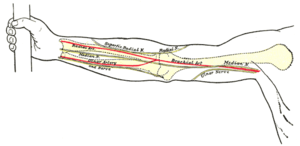

أسهل طريقة لقياس النبض تتم عن طريق جَس النبض وذلك بوضع الأصابع (السبابة والوسطى) على أحد الشرايين وتعداد النبض في الدقيقة الواحدة. أشهر الشرايين في القياس:

| الشريان الكعبري | الشريان السباتي | الشريان الفخذي |

يفضل تجنب استخدام الإبهام في جس النبض، وذلك لأن الإبهام يحوي على شريان في باطنه، مما يؤدي إلى حدوث خطأ في القياس، فيقوم الجاس بعدّ نبضه هو بدل نبض المريض.